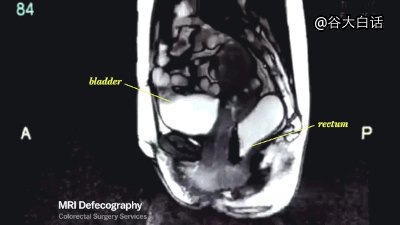

#爱你爱到骨头里#【MRI下诡异而奇妙的人体】这是一段用核磁共振成像技术制作的动态短片,将人类喝水、亲嘴、嘿咻、拉翔、生娃、说中文、说德文等日常活动展现得毫纤毕现、一览无遗。doge微猎奇,微暴,慎点。